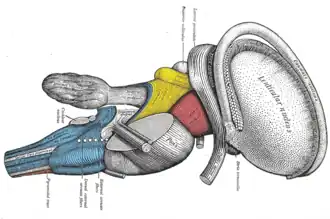

Dissection of brain-stem. Lateral view.

Dissection of brain-stem. Lateral view. -